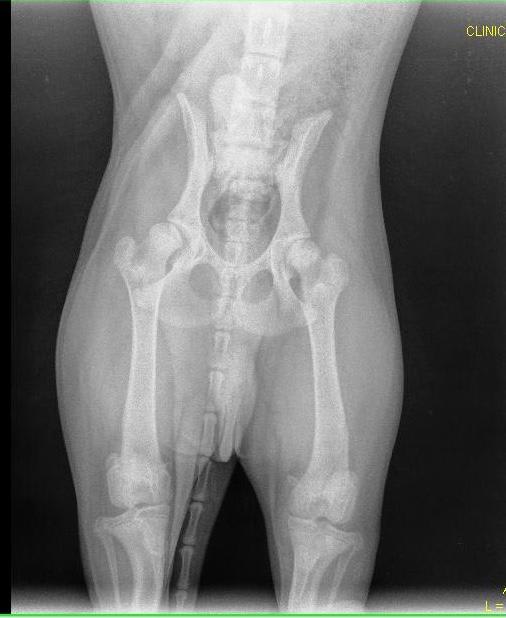

Pet's info: Dog | Golden Retriever | Male | unneutered | 5 months and 9 days old | 53 lbs

How bad is this hip dysplasia? 5 month, golden, 24kg. He is sliding when seat to frog position but seems fine. Can I do something to prevent his condition to worsening.

Thank you for using Petco Pet Education Center, formerly Petcoach. So sorry that Baxter has this issue. The right hip has severe dysplasia (the x-ray is not marked so I am assuming it is the right one). The other hip looks OK. The only way to fix this is with surgery - either a FHO procedure or a total hip replacement. You need to speak to your vet about options. There is no medication to reverse, cure or stop the progression of this disease. Surgery will definitely be needed.